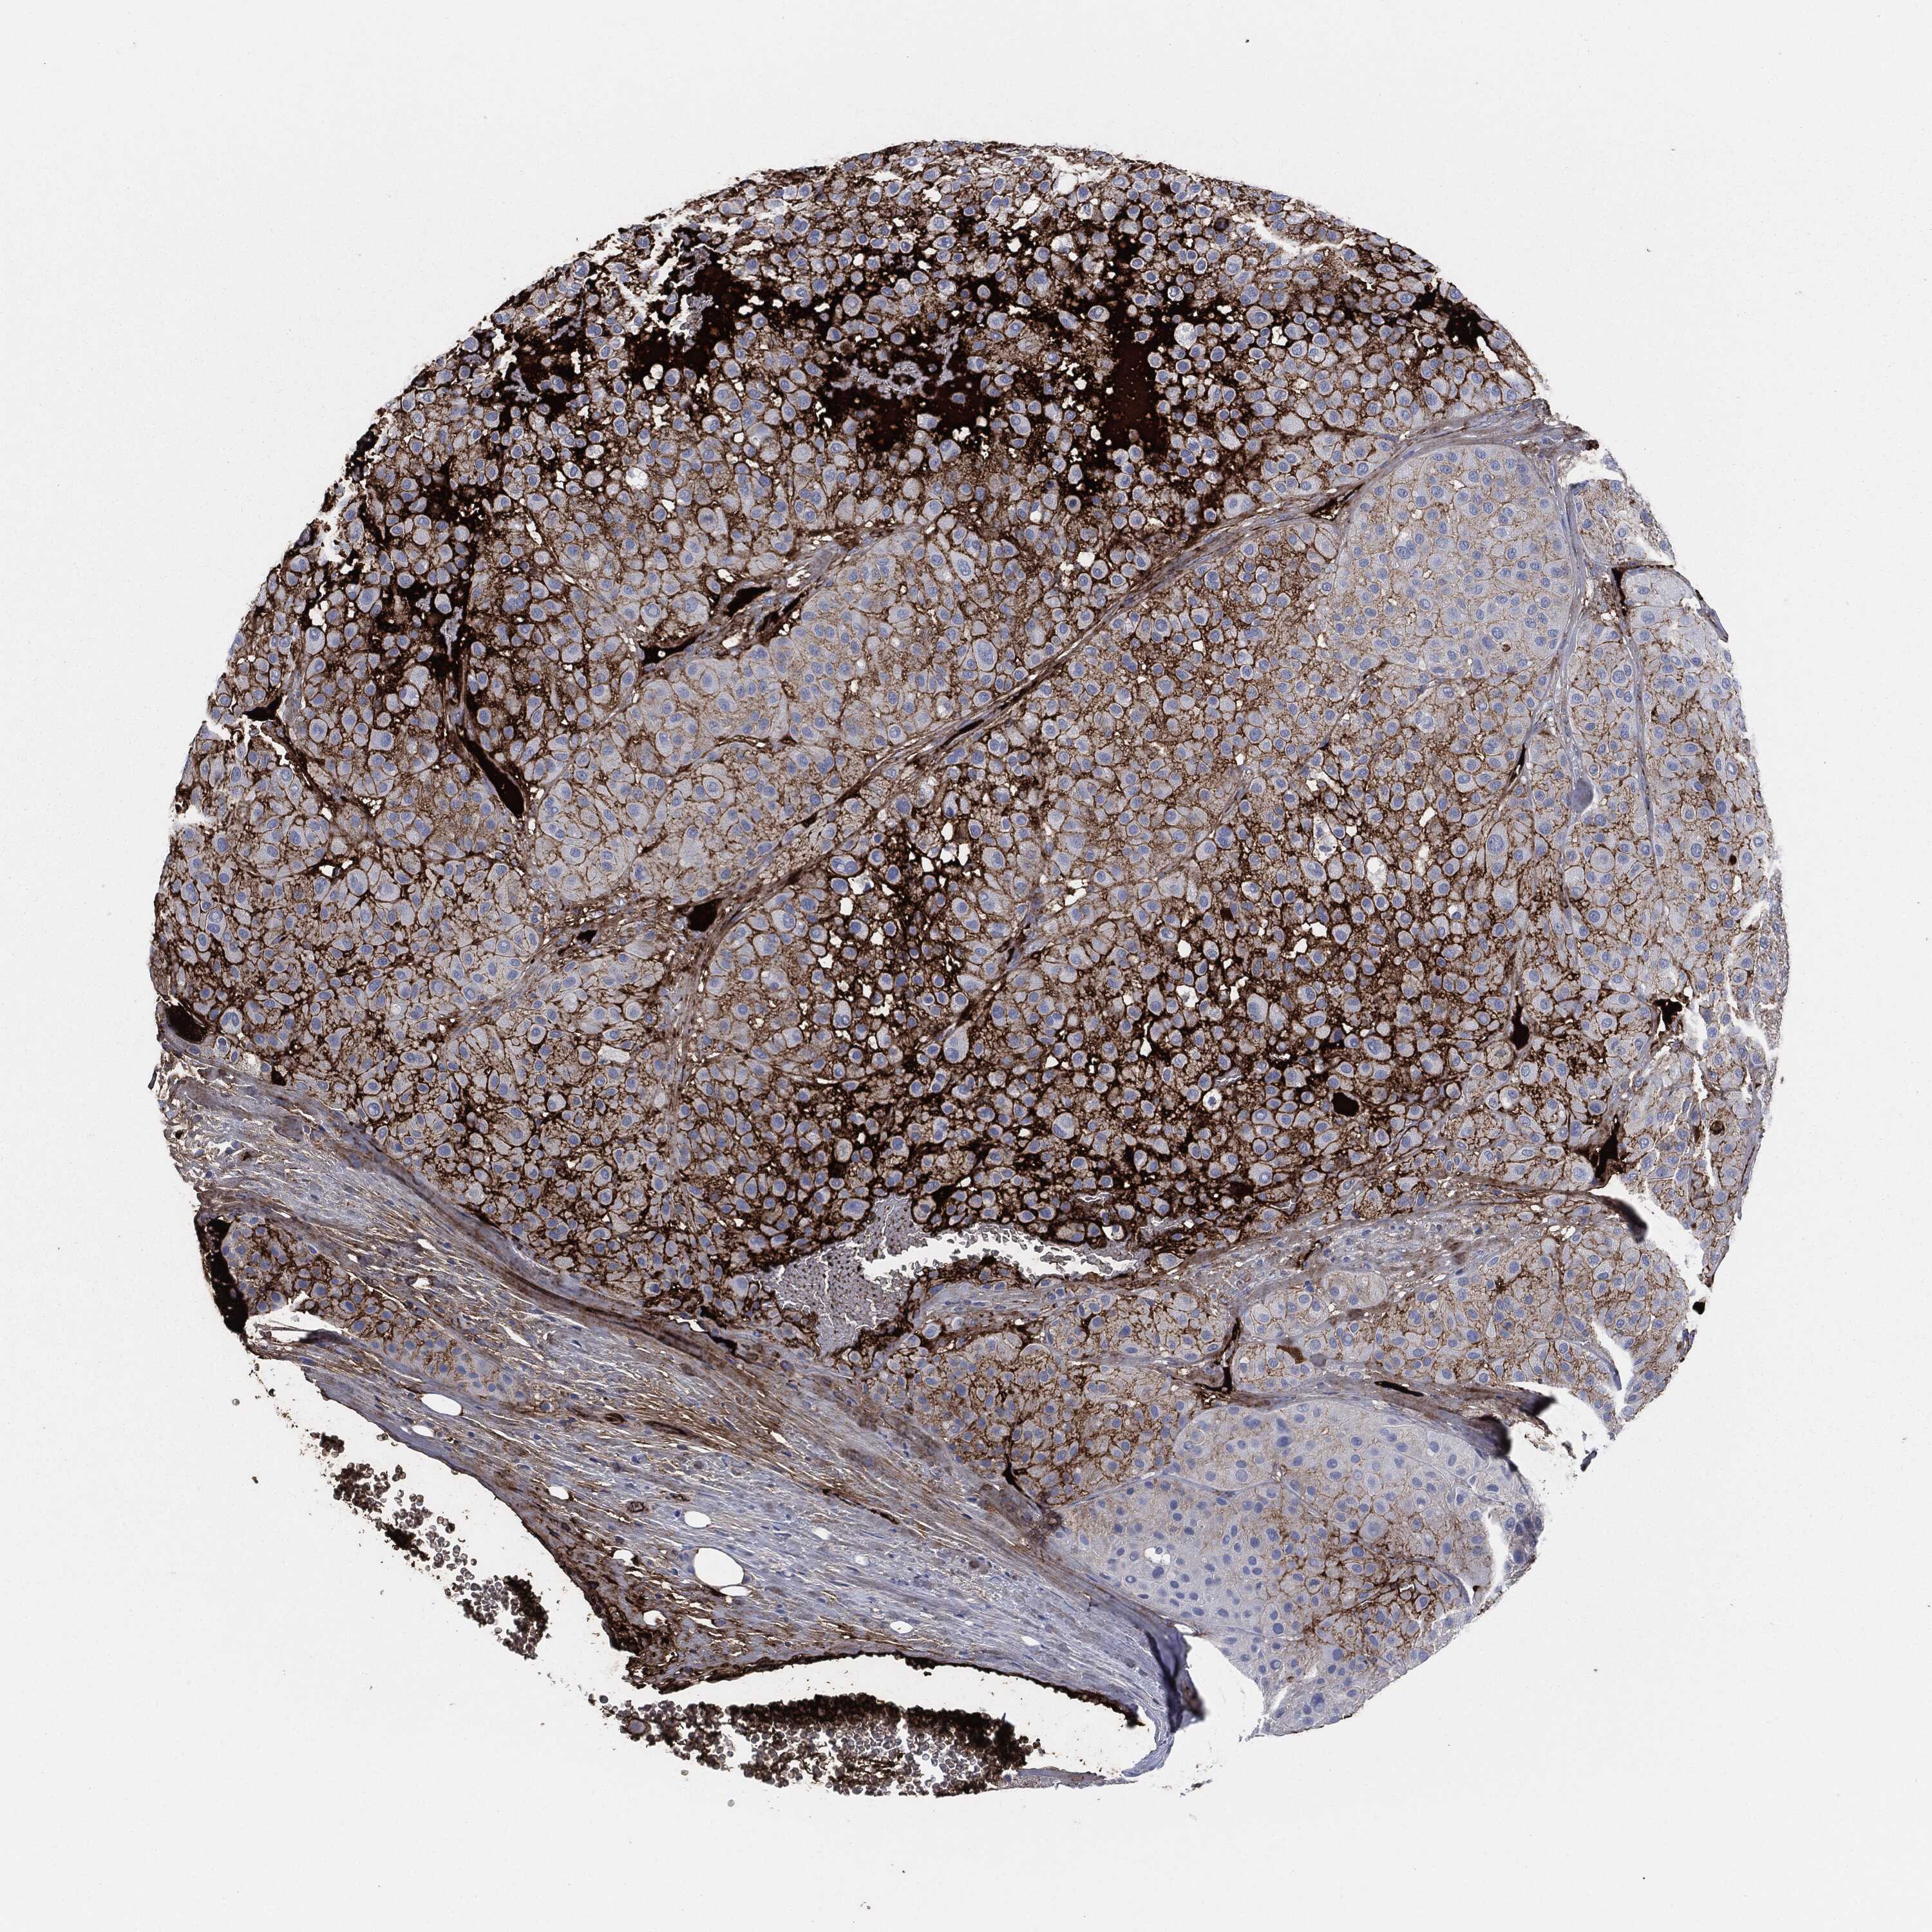

MELANOMA - Protein expressioni

A mouse-over function shows sample information and annotation data. Click on an image to view it in a full screen mode. Samples can be filtered based on level of antibody staining by selecting one or several of the following categories: high, medium, low and not detected. The assay and annotation is described here.

Note that samples used for immunohistochemistry by the Human Protein Atlas do not correspond to samples in the TCGA dataset.

Antibody stainingi

Antibody staining in the annotated cell types in the current human tissue is reported as not detected, low, medium, or high, based on conventional immunohistochemistry profiling in selected tissues. This score is based on the combination of the staining intensity and fraction of stained cells.

Each image is clickable and will lead to virtual microscopy that enables deeper exploration of all samples and also displays staining intensity scores, fraction scores and subcellular localization as well as patient and tissue information for each sample.

HPA049793

CAB016070

CAB080297

CAB080298

CAB080299

Staining

High

Medium

Low

Not detected

Intensity

Strong

Moderate

Weak

Negative

Quantity

>75%

75%-25%

<25%

None

Location

Nuclear

Cytoplasmic/membranous

Cytoplasmic/membranous,nuclear

Malignant melanoma, NOS

Malignant melanoma, Metastatic site